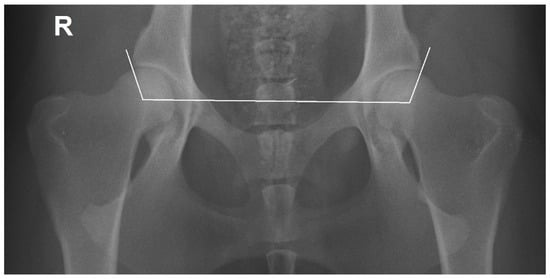

2.1. Radiographic Measurements

- Genevois, J.-P.; Cachon, T.; Fau, D.; Carozzo, C.; Viguier, E.; Collard, F.; Remy, D. Canine Hip Dysplasia Radiographic Screening. Prevalence of Rotation of the Pelvis along Its Length Axis in 7012 Conventional Hip Extended Radiographs. Vet. Comp. Orthop. Traumatol. 2007, 20, 296–298. [Google Scholar] [PubMed]

- Martins, J.; Colaço, B.; Alves-Pimenta, S.; Gonzalo Orden, J.M.; Ferreira, A.J.; Ginja, M.M. Effect of the Dog positioning on X-ray Table on Hip Dysplasia Parameter Evaluation. Vet. Comp. Orthop. Traumatol. 2019, 32, 376–382. [Google Scholar] [CrossRef] [PubMed]